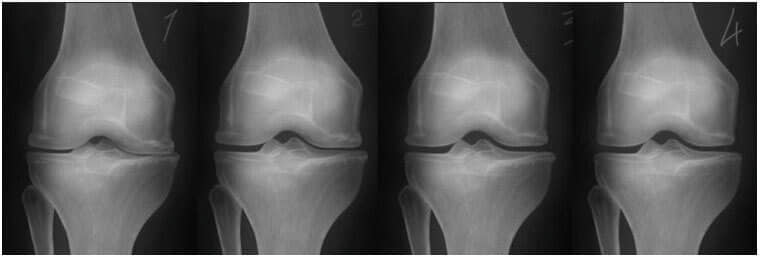

1. Nedostatak hranjivih tvari u zglobu. Hrskavično tkivo je uništeno.

2. Obnova hrskavičnog tkiva u zglobu nakon 2 sedmice upotrebe gele Bone Control.

3. Obnova hrskavičnog tkiva zgloba nakon 3 sedmice upotrebe gele Bone Control.

4. Zdrav zglob nakon jednog kursa gele Bone Control.

- Snimak ispod pokazuje tipičnu sliku oporavka zgloba koljena.